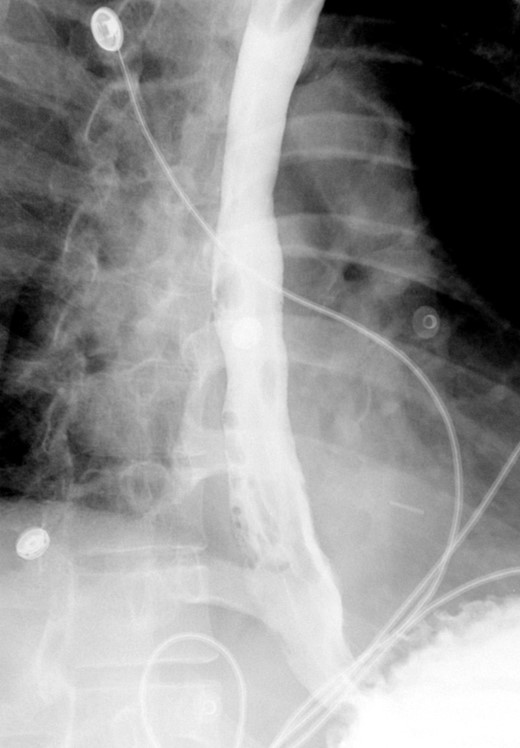

A computed tomographic scan revealed air and fluid surrounding the esophagus (Fig. 1). Esophagogram performed with water-soluble contrast media showed a distal esophageal perforation with a free leak into a large mediastinal cavity to the left of the esophagus (Fig. 2). The patient was triaged directly to the operation room. A left chest tube was placed with improvement in his oxygenation, and grossly murky fluid was drained. Esophagogastroduodenoscopy (EGD) was performed next and revealed a very small caliber esophagus with concentric ringed appearance. A tight stricture was noted in the mid-esophagus, which only allowed passage of a pediatric gastroscope. In the lower esophagus, a 2-cm tear with necrotic edges was visualized 3 cm above the gastroesophageal (GE) junction. With this diffusely strictured and very diseased appearance of the esophagus, the decision was made to proceed with stent placement and thoracoscopic drainage of the mediastinum rather than primary surgical repair via thoracotomy. A fully covered, 15 cm × 19 mm, EndoMAXX® esophageal stent was successfully placed covering the perforation site. Mediastinal washout and drainage was performed subsequently via left thoracoscopy. A postoperative esophagram showed no leak and the patient was started on a liquid diet that was tolerated well. His hospital stay was uneventful, and he was discharged on twice daily high-dose proton pump inhibitor (PPI) on post-operative Day 5. He was placed on a mechanical soft diet on discharge. Repeat upper GI study with water soluble contrast postoperatively showed no evidence extravasation. (Fig. 3)

Shows metallic expandable stent in a satisfactory position in the mid to lower thoracic esophagus extending to the GE junction. Water-soluble contrast is seen filling the stent with no evidence of extravasation.